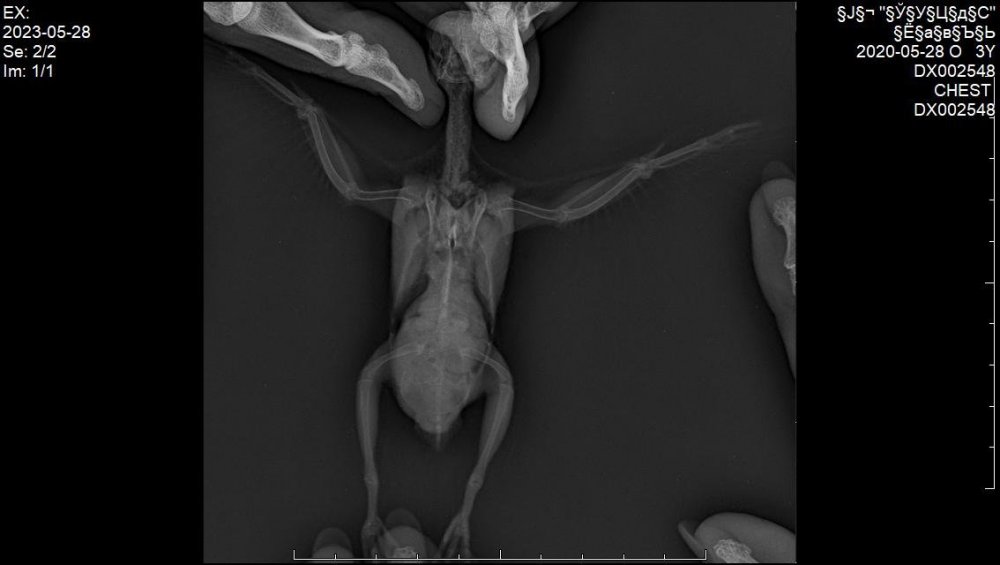

В общем, неделю назад сделали рентген (прикладываю фото). Самим сразу уже стало понятно, что дела плохи. В среду со мной связалась врач, сообщила что у нас обширная опухоль в области целома с большим давлением на органы. Случай неизлечимый.

Назначили: мелоксидил суспензию, габапентин и гептрал для паллиативного лечения.

Вот только я не поняла откуда у него эта опухоль растёт. Врач нам не сказала ни про какой-то орган, то ли это проблема с печенью, то ли семенники.

Прошу врачей форума помочь как-то более детально разобраться в наших снимках, чтобы просто в целом видеть картину и во избежании подобных ситуаций в будущем.

IMG-20230603-WA0006.jpg

IMG-20230603-WA0007.jpg